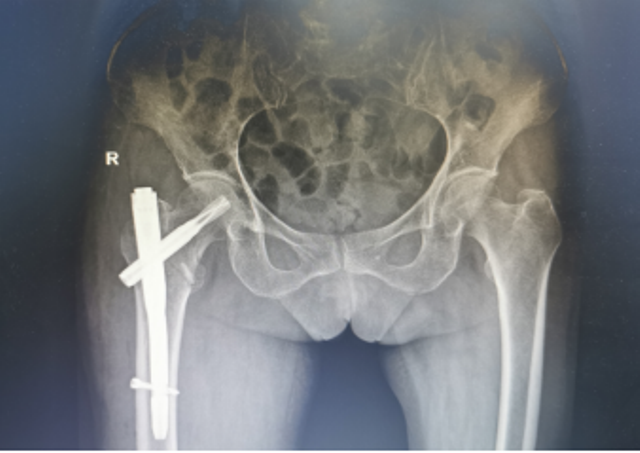

近日,陕西省第四人民21点基本策略 骨科再次成功为一例91岁高龄的右股骨粗隆间骨折合并冠心病脑梗塞、贫血者实施右股骨粗隆间骨折闭合复位股骨近端抗旋转髓内钉内固定术(简称:PFNA内固定术)。经过术后精心的治疗与护理,患者现已转到康复医学科继续康复治疗。

为了手术能顺利开展,骨一科何大鹏主任通过医务科邀请心血管内科、麻醉科、呼吸与危重症医学科、重症医学科等启动围手术期管理专家团队进行会诊,拟定“右股骨粗隆间骨折闭合复位PFNA内固定术”的手术方案,并制定了一套缜密的术前、术中、术后诊疗康复方案,完善术前准备。3月26日,在麻醉科、手术室团队的密切配合下,何大鹏主任、刘玉春、赵鑫医师为万奶奶成功实施手术,整个术程一气呵成,既缩短手术时间,也减少术中出血,有效降低手术给患者带来的伤害。